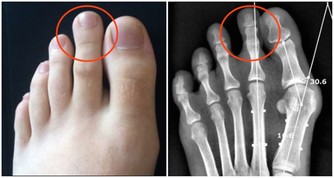

4、捏腳踝

腳踝分佈著淋巴管、血管、神經等重要組織,是腳部與人體血液流動的重要關口,流經靜脈回心血液。

當心臟不能好好工作時,靜脈血液不能順利回流,引起靜脈內壓力升高,體液漏出進入組織間隙,表現為下肢水腫,尤其是腳踝水腫症狀。

檢測方法是:手指按壓腳踝或小腿,手指鬆開後按壓部位呈凹陷狀,通常不能立即恢復。出現這種情況時,須及時就醫做下肢超聲檢查。